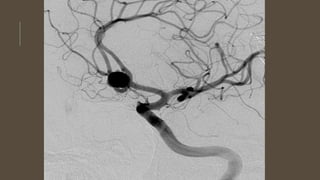

INVESTIGATIONS

• CT angiogram

• DSA

INVESTIGATIONS • CT scan •CT angiogram • MRI and MRA • DSA